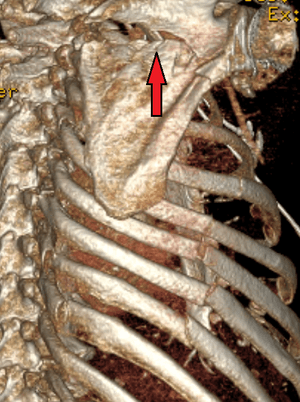

| A right sided scapula fracture with rib fractures underneath seen on a 3D reconstruction of a CT scan | |

Most fractures of the scapula can be seen on a chest X-ray; however, they may be missed during examination of the film.[1] Serious associated injuries may distract from the scapular injury,[4] and diagnosis is often delayed.[3] Computed tomography may also be used.[1] Scapular fractures can be detected in the standard chest and shoulder radiographs that are given to patients who have suffered significant physical trauma, but much of the scapula is hidden by the ribs on standard chest X-rays.[4] Therefore, if scapular injury is suspected, more specific images of the scapular area can be taken.[4]